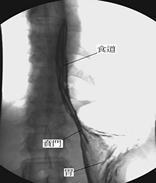

上消化道攝影是一種特殊的x光檢查,其檢查的範圍包括食道、胃、十二指腸以及其他小腸(空腸和迴腸)。

(1)當開始檢查時,會先給一小包蘇打粉,請合著一小杯的開水迅速吞下,此蘇打粉的作用是利用氣體使胃、腸道脹起來 以利觀察黏膜的情形。醫護人員會遞上一杯如奶昔般的腸胃道造影劑(鋇劑),請配合指示飲用,例如請您喝一口含在嘴巴,請您吞下時才可以吞下,檢查過程中檢查台上會開始平躺、俯臥、側躺或翻轉,有時則需要被檢查者配合閉氣,同時以X光視需要做不等次數之照相。只檢查食道、胃及十二指腸者約費時20~30分鐘,若包括空腸和迴腸者約費時2小時以上。